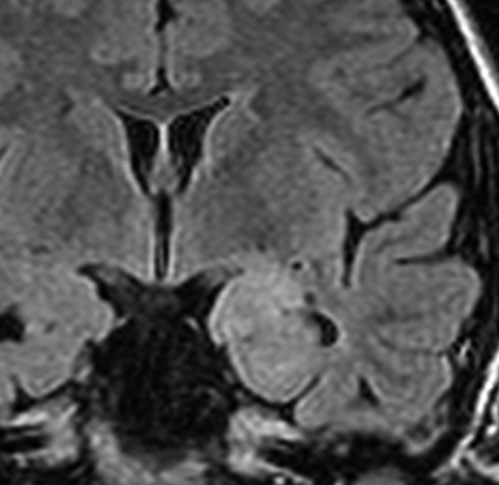

脳幹部から発生した退形成性神経節膠腫 grade 3

軽い右顔面神経麻痺で発症した小児で,右上下肢の軽度の失調症もありました。脳幹部(橋)の右背側から発生した腫瘍で,軽度の閉塞性水頭症を合併しています。左はT2強調画像で,橋の右側ににじむような浸潤像と浮腫があります。腫瘍は小嚢胞を形成してT2強調画像で実質は等信号です。真ん中の画像はCISS画像で橋が腫大しているのがよくわかります。右側はガドリニウム増強像で,全体が増強されてまだらな増強所見となっています。正中後頭下開頭で全摘出 gross total removal して,局所放射線治療とtemozolomide, cisplatine, etoposide, gleevec, hydoreaなどの化学療法を行いましたが,手術後4ヶ月で激しい播種再発を来しました。